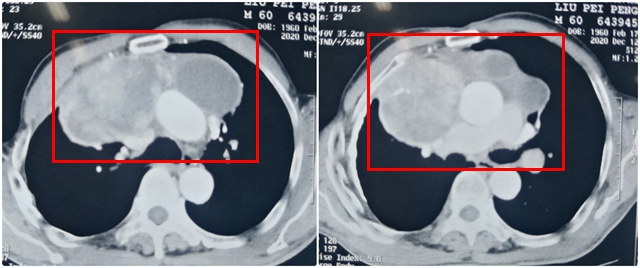

術(shù)后影像

由于如此巨大的縱隔腫瘤并不多見(jiàn),且腫物侵及心包、上腔靜脈、左無(wú)名靜脈、升主動(dòng)脈及左右膈神經(jīng),手術(shù)風(fēng)險(xiǎn)非常高。經(jīng)過(guò)充分的術(shù)前準(zhǔn)備,白舒副院長(zhǎng)帶領(lǐng)胸外科團(tuán)隊(duì)在麻醉科、手術(shù)室的協(xié)助下開(kāi)始手術(shù)。憑借充足的術(shù)前準(zhǔn)備和精湛的醫(yī)療技術(shù),整個(gè)手術(shù)進(jìn)展得很順利,歷時(shí)3小時(shí)全部完成,腫瘤連同受侵心包完整切除,雙側(cè)膈神經(jīng)保護(hù)完好,術(shù)后患者恢復(fù)良好,生活質(zhì)量得到明顯改善,患者和家屬由衷感謝市二院胸外科醫(yī)生的精心救治。